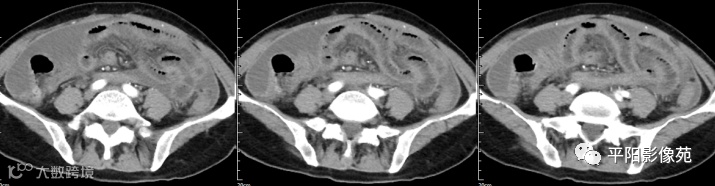

湿型:渗出性高密度腹水(CT值20-45HU),高密度由于高蛋白和细胞含量多可能。

干型:干酪性肠系膜淋巴结病、纤维粘连、增厚,网膜饼状改变

纤维型:网膜饼状团块